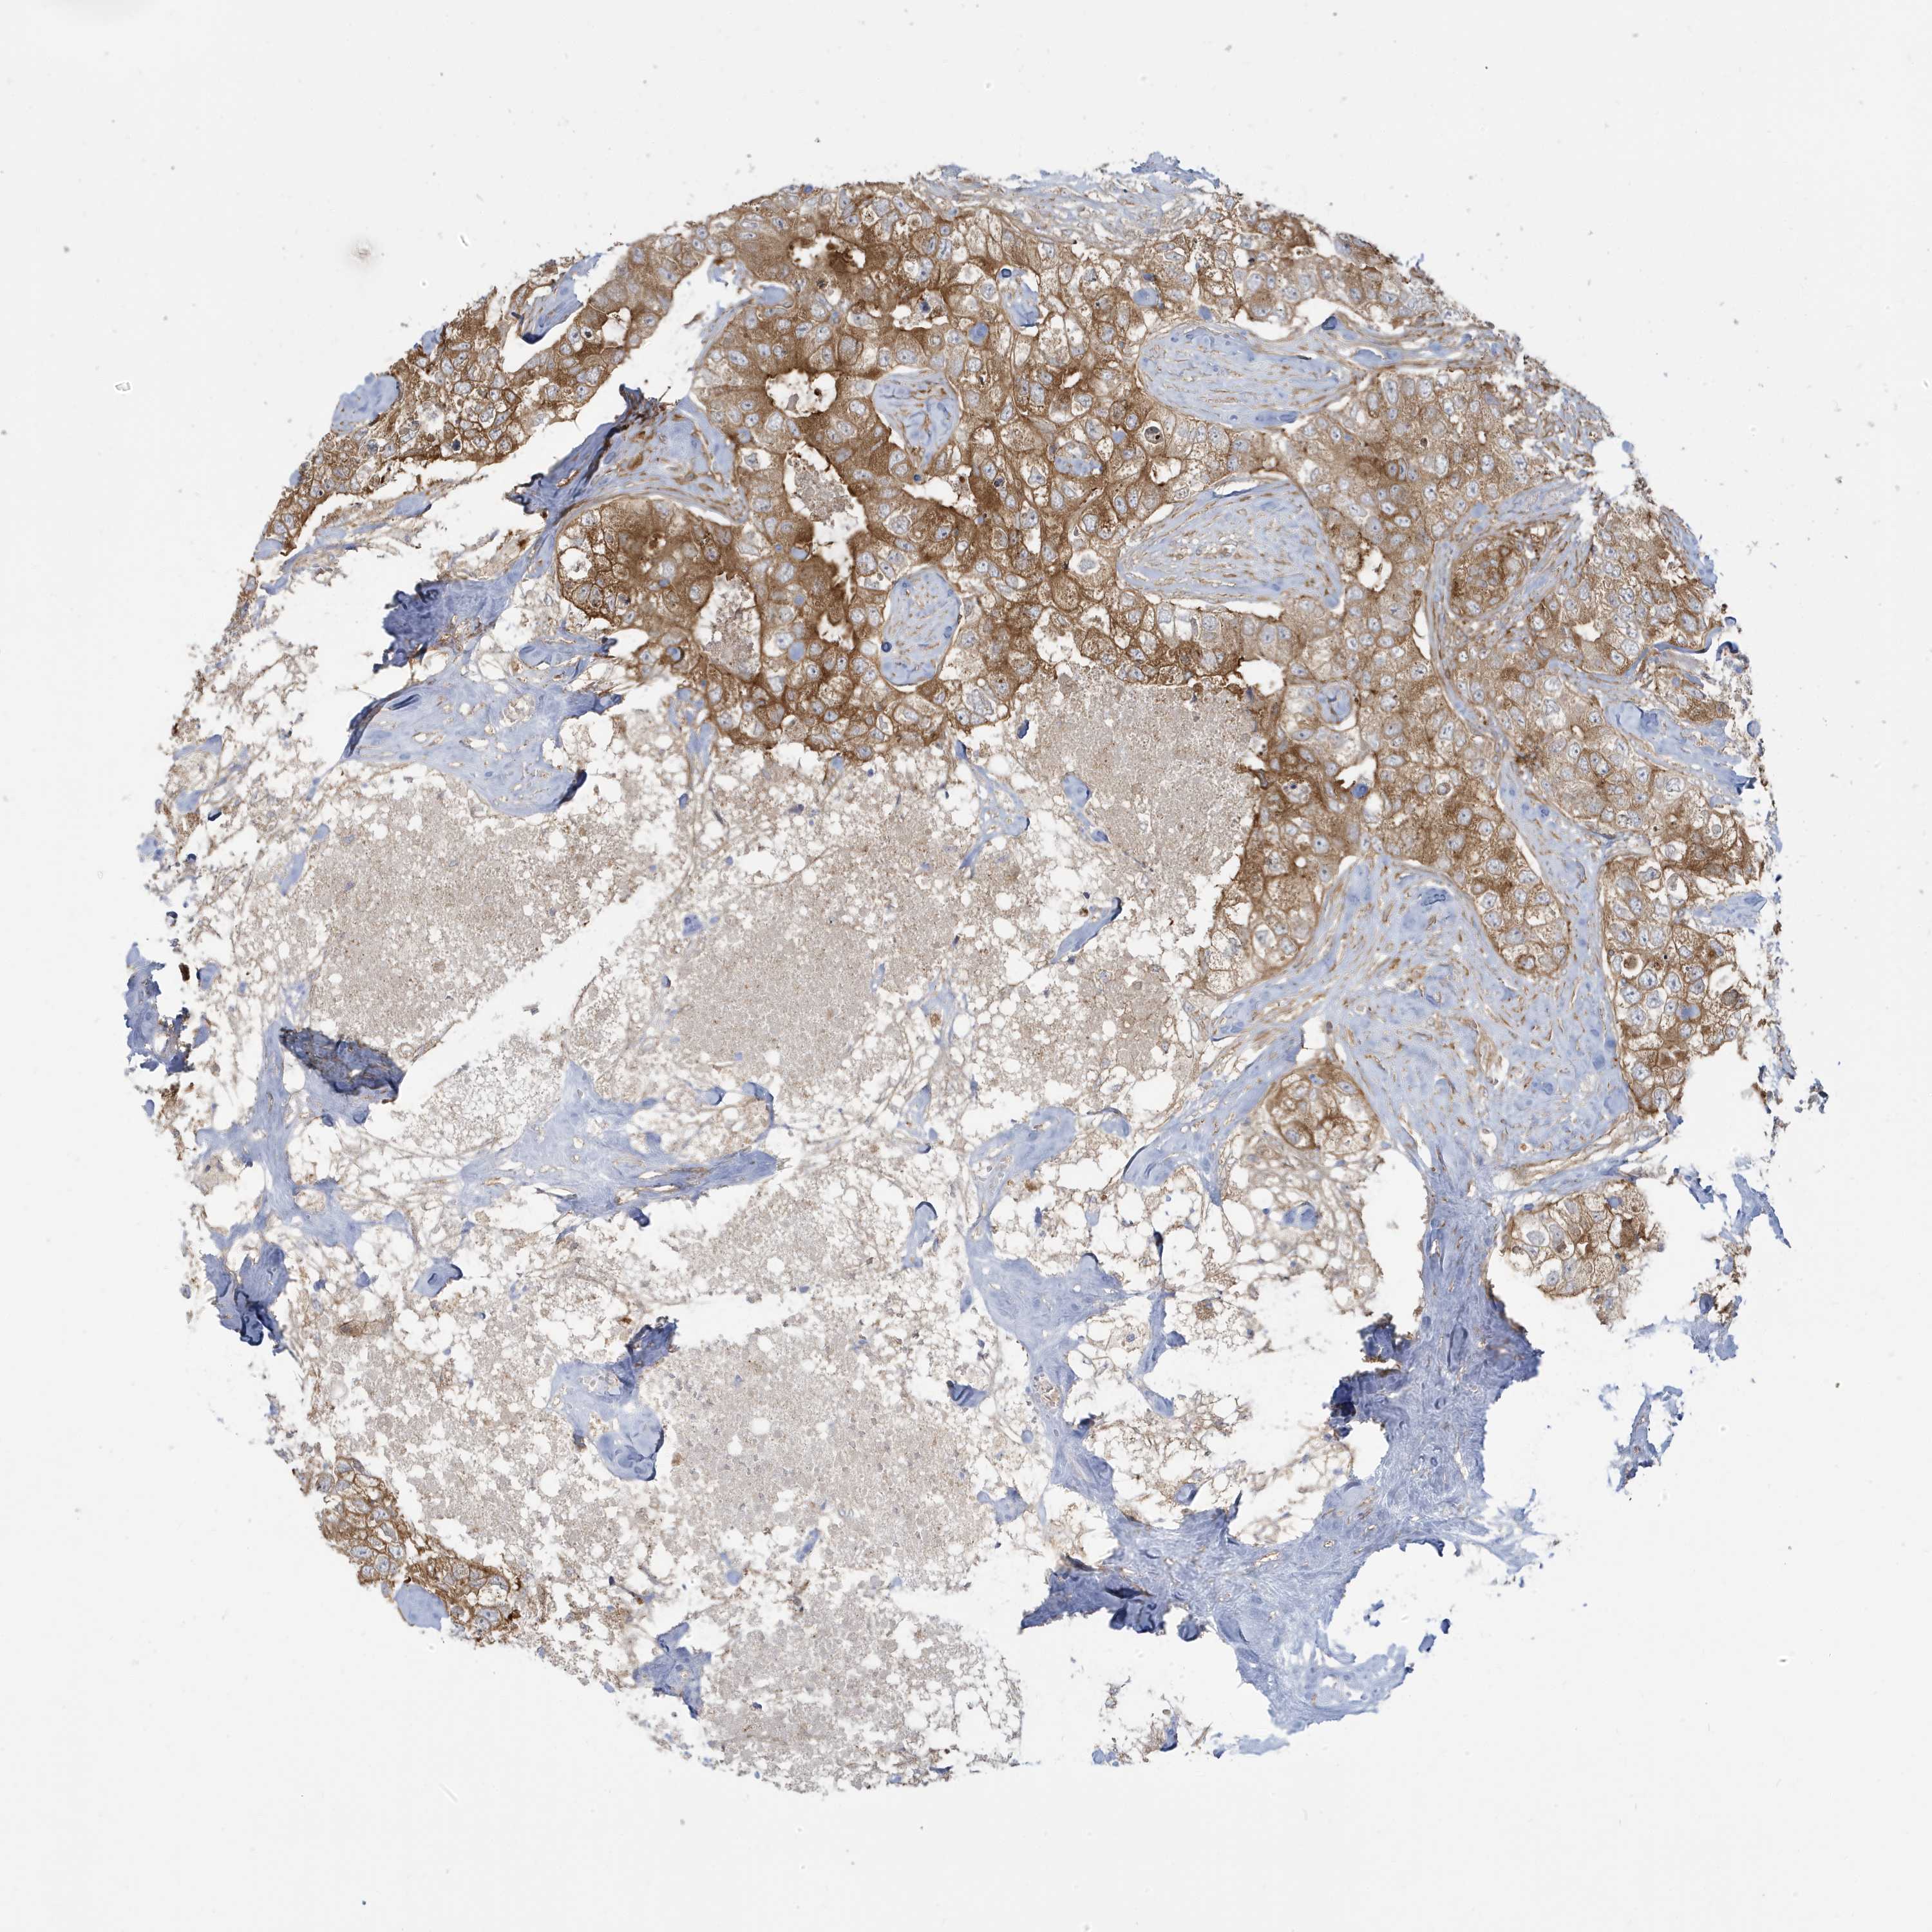

CANCER BREAST CANCER Show tissue menu

BRCA TCGA BRCA VALIDATION PROTEIN EXPRESSION